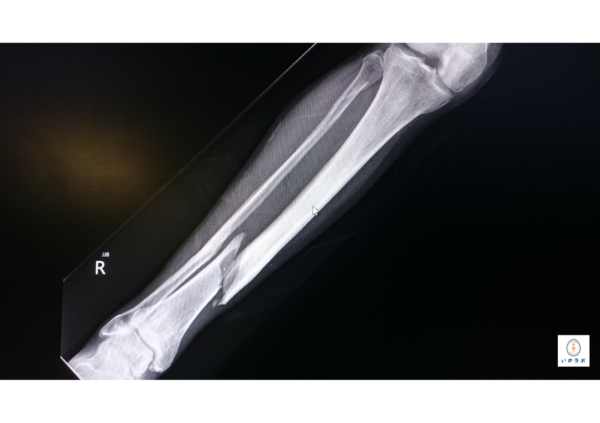

①X線: 初期は陰性になり得るが、疲労骨折は時間経過とともに低線量の骨梁の変化や微細な裂隙が見えることがある。急性の骨折は典型的に陰影変化を伴う。

②MRI/CT: 疲労骨折の診断に有用。MRIでは骨髄浮腫とともに明瞭な局在性の骨挫傷・骨折線が確認される。シンスプリントはMRIで筋膜・骨膜の疼痛性炎症や筋群の過負荷変化が見える程度。